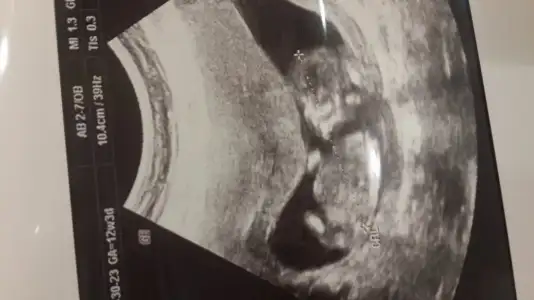

Suan 12 haftaligim gecen hafta dr.ye gittik daha belli degil dedi ama cok merak ediyorum kiz erkek degismiyor ilk bebegimiz olacagi icin ☺bizede bakar misiniz ?